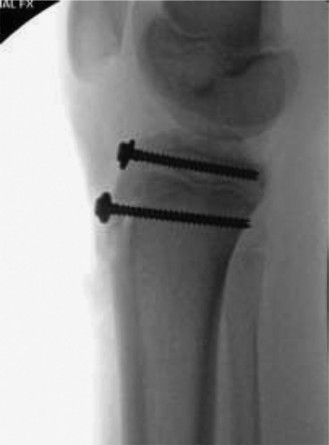

The correct answer is (D). This patient has a type III fracture, and given the amount of displacement, an open reduction is necessary. Choices A and B can be excluded because a closed reduction with casting or pinning are not sufficient treatment methods for this fracture. Given the association of type III fractures with intra-articular pathology, it is recommended to perform an arthrotomy at the time of surgery to ensure that there is no meniscal injury or soft tissue incarceration and to

ensure that the joint surface is anatomically reduced. Some advocate using arthroscopy for this purpose rather than doing a full arthrotomy—this would depend on surgeon’s preference, but regardless of technique, it is important to evaluate. Screw fixation is preferred over pins or sutures, particularly in larger adolescents because of the significant pulling force that the quadricep exerts on the tibial tubercle. In children/very young adolescents (who very rarely get this injury) you may consider suture fixation with cast augmentation if there is concern regarding the growth plates, but the injury occurs far more commonly in adolescents in whom the growth plate is already closing, so screw fixation is preferred to give more stable fixation and allow an earlier return to range of motion (Fig. 10–13).

#### Figure 10–13 Objectives: Did you learn...? What a tibial tubercle fracture is and potential risk factors? Risk of compartment syndrome with tibial tuberosity fractures?